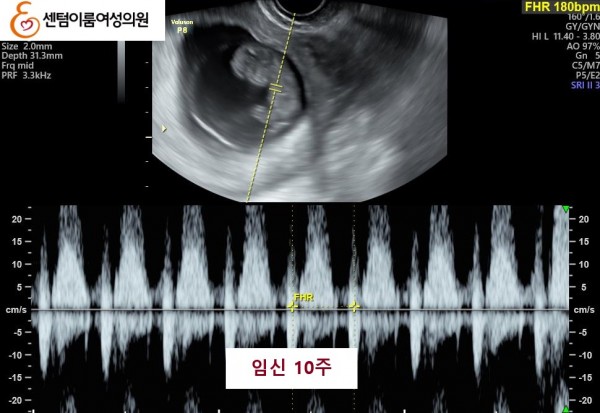

42세, 정 O O님 고령 연령에서 임신된 사례

2025.5월 본원 내원 전 타병원에서 다수의 시술 받으신 이력이 있으셨습니다.

40세 이상 고령 연령은 염색체 비정상 난자 비율이 높아 고난도 난임의 대표적인 사례입니다.

꾸준한 식생활 개선과 약물 치료를 받으시고, 한번의 시술로 임신에 성공 하셨습니다.